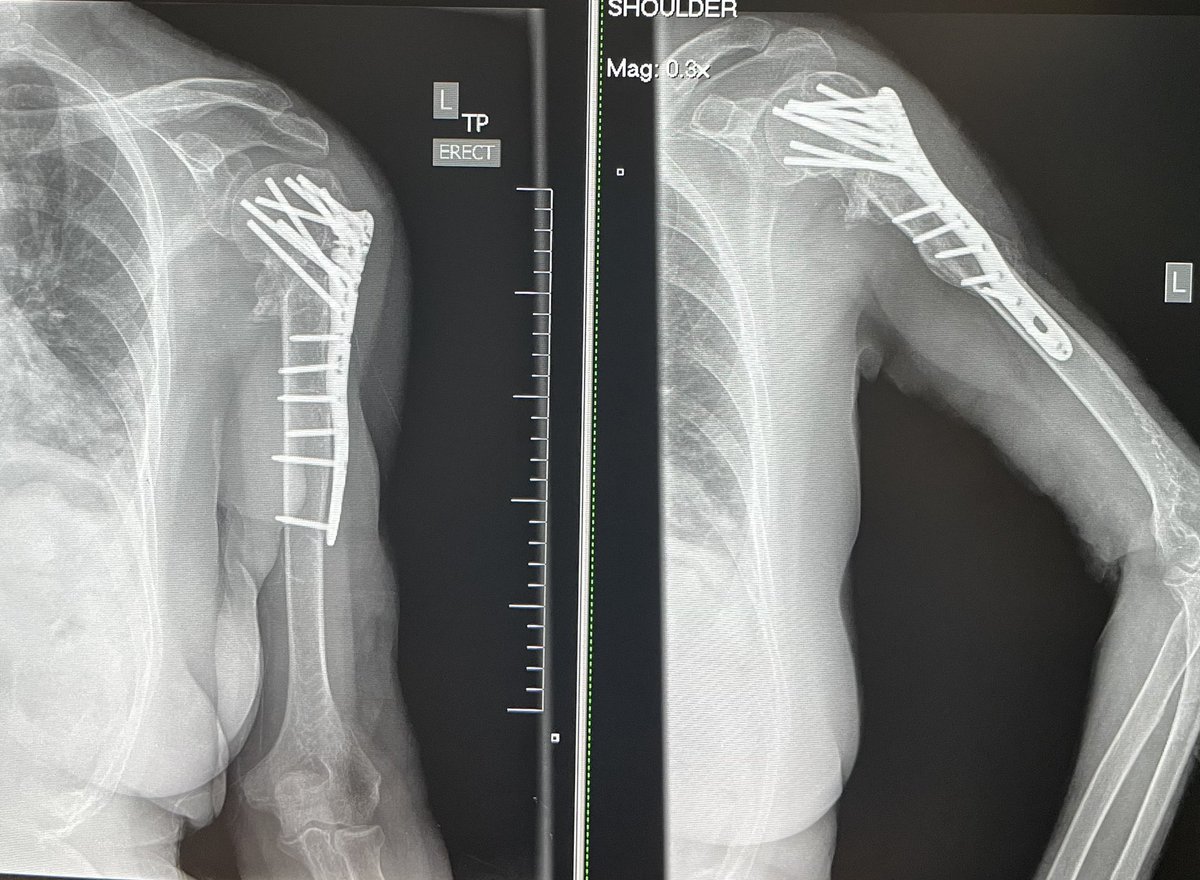

8 months post Left proximal humeral nonunion repair with revision ORIF and RIA reamer. That humeral head was definitely worth saving! 👍🤗#orthotwitter #Limblengthening #OTA #nonunion

JanetConwayy's tweet image. 8 months post Left proximal humeral nonunion repair with revision ORIF and RIA reamer. That humeral head was definitely worth saving! 👍🤗#orthotwitter #Limblengthening #OTA #nonunion